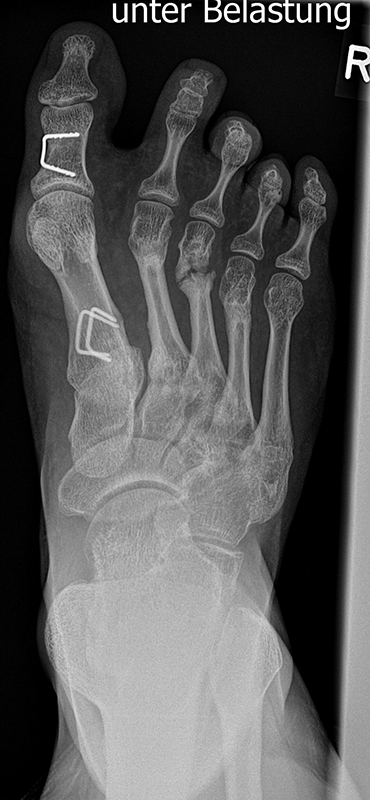

MT I Basis closed wedge Osteotomie

Besteht bei einem Kind oder Jugendlichen ein Hallux valgus mit einer Überlänge Metatarssale I, kann minimalinvasiv eine adduzierende closing wedge Osteotomie lateral basisnah durchgeführt werden (Abb. 24).

Abb. 24 a-d: Röntgen präoperativ bei Hallux valgus und dezentrierten Sesambeinen mit Schmerzen seit einem Jahr unter dem Großzehengrundgelenk (a), druckentlastende minimalinvasive Metatarsale I closing wedge Osteotomie an der Basis (b), intraoperative Korrekturstellung (c) und intraoperatives Bild nach Entfernung der Kirschner-Drähte sechs Wochen postoperativ (d).

Zum Lesen der Bildbeschreibung und zur Vollansicht bitte die Bilder anklicken. Bilder: A. Helmers.

Zusätzlich kann mit einem eingebrachten Kirschner-Draht als Joystick das Metatarsale I Köpfchen distal in 10-15° Supination gedreht werden. Hierbei infraktioniert die mediale verbleibende Kortikalis und das Korrekturergebnis muss mit einem 1.6 oder 1.8 Kirschner-Draht fixiert werden. Mit der milden Korrektur in die Supination rezentrieren sich die Sesambeine und die Rezidivgefahr verringert sich.